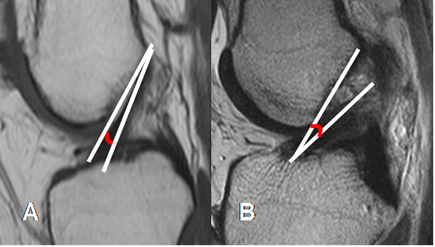

La orientación del LCA es uno de los signos con mayor sensibilidad y especificidad, de lesión ligamentaria.

Fig 13. LCA normal.

A: RM sagital en T1, B: RM sagital en T2 y C: RM sagital en FFE. Ligamento normal,

hipointenso en todas las secuencias.

Fig 14. LCA normal.

RM coronal en T1. Bandas normales del LCA. Anteromedial (Flecha delgada) y posterolateral (Flecha gruesa).

Fig 15. LCA normal.

A: RM sagital en T1. Relación normal, con el platillo tibial.

B: RM sagital en T2. Ruptura del LCA, el cual está horizontalizado y con disminución del ángulo.

Fig 16. LCA normal.

A: RM sagital en T1. Angulo normal de vértice superior, con la línea intercondilea.

B: RM sagital en T2. Ruptura del LCA, con ángulo de vértice inferior.